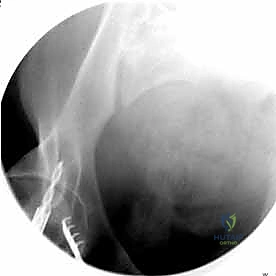

- الأشعة السينية (X-rays): يتم أخذ صور أمامية وخلفية (AP View) وصور بزوايا محددة (Inlet and Outlet views) لتقييم الإزاحة في حلقة الحوض.

- الأشعة المقطعية المحوسبة (CT Scan): وهي المعيار الذهبي. توفر صوراً ثلاثية الأبعاد (3D Reconstruction) تسمح للدكتور هطيف برؤية الكسر من جميع الزوايا، وتحديد مسار المسامير المعدنية بدقة متناهية قبل بدء الجراحة.